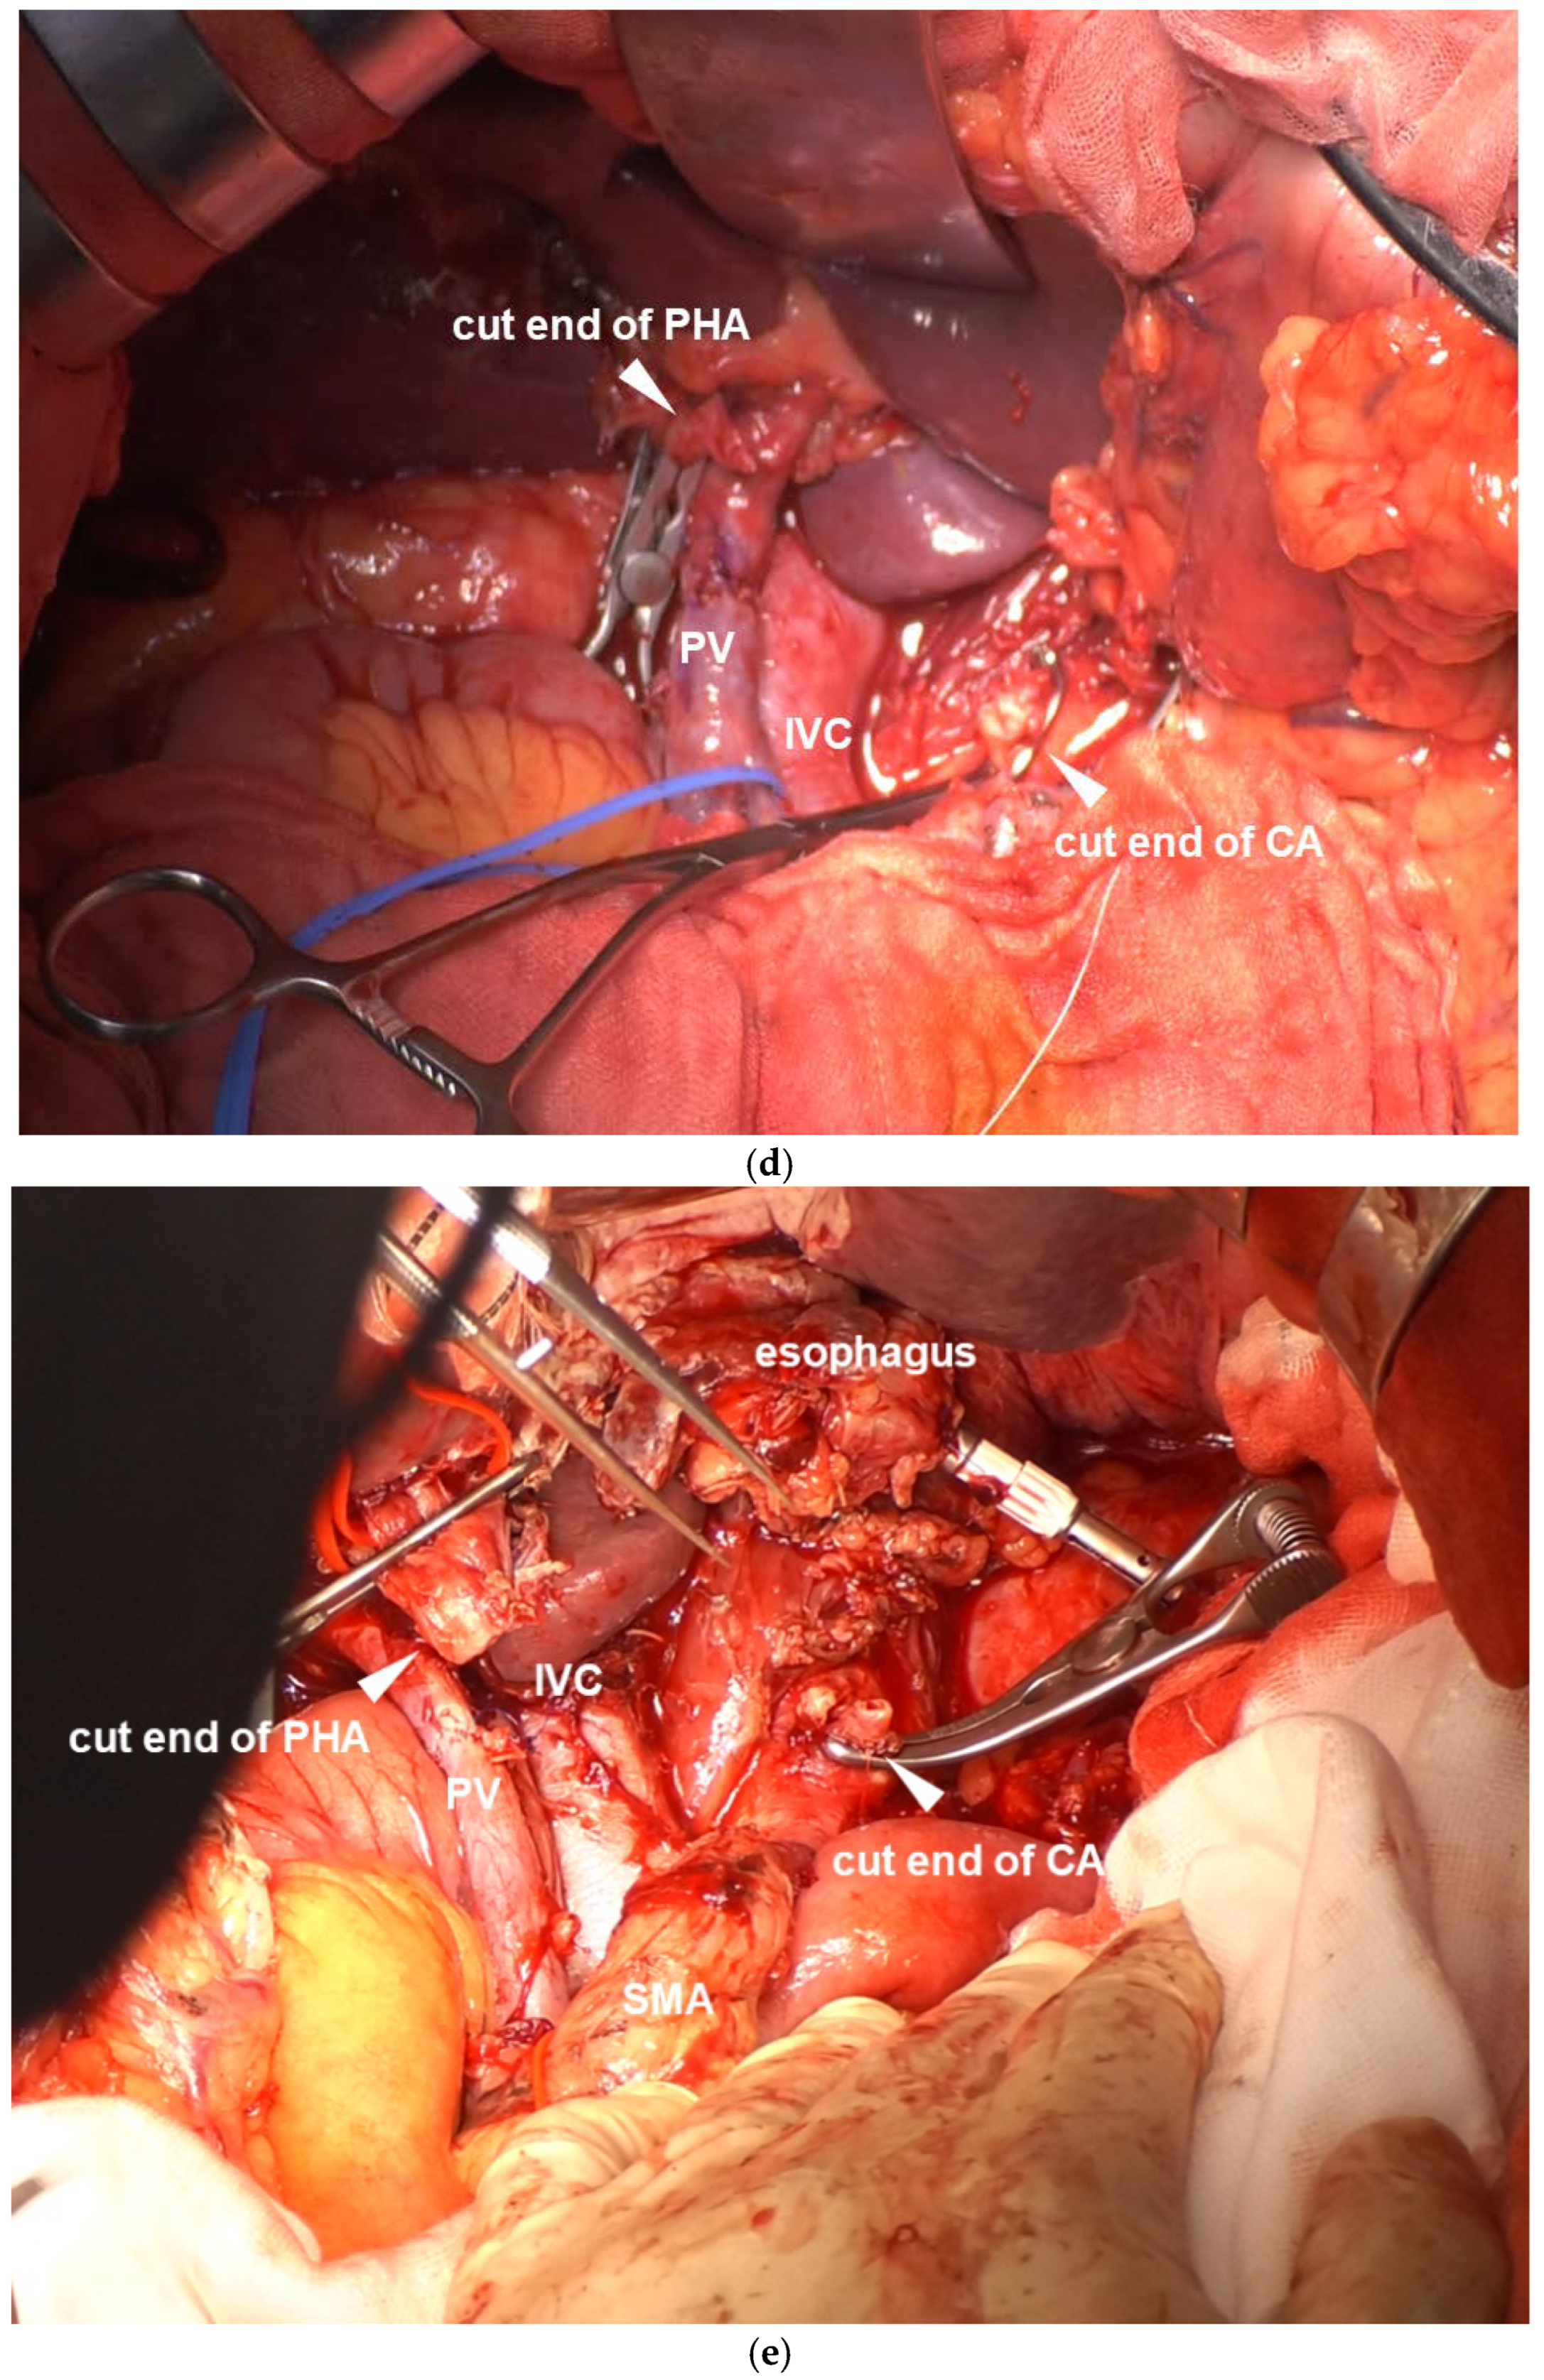

CA Reconstruction in TP-CAR+TG